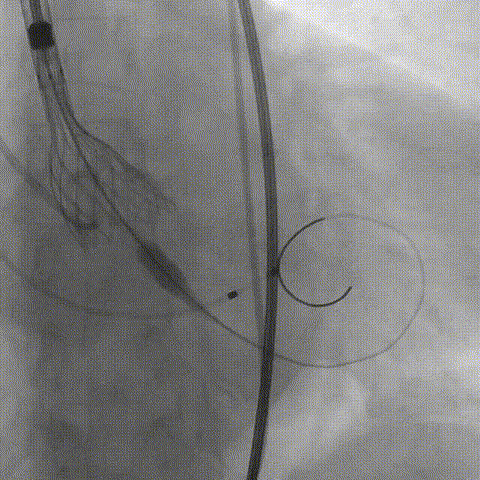

球囊预扩

TaurusElite输送系统柔顺过弓跨瓣后,第一次AV23瓣膜瓣环平面上2mm定位释放,到工作位后造影评估瓣膜形态、发现无冠窦支撑力不够理想瓣膜完全释放有上跳风险,于是决定回收瓣膜,调整瓣膜定位,重新释放;

第一次定位

第一次释放